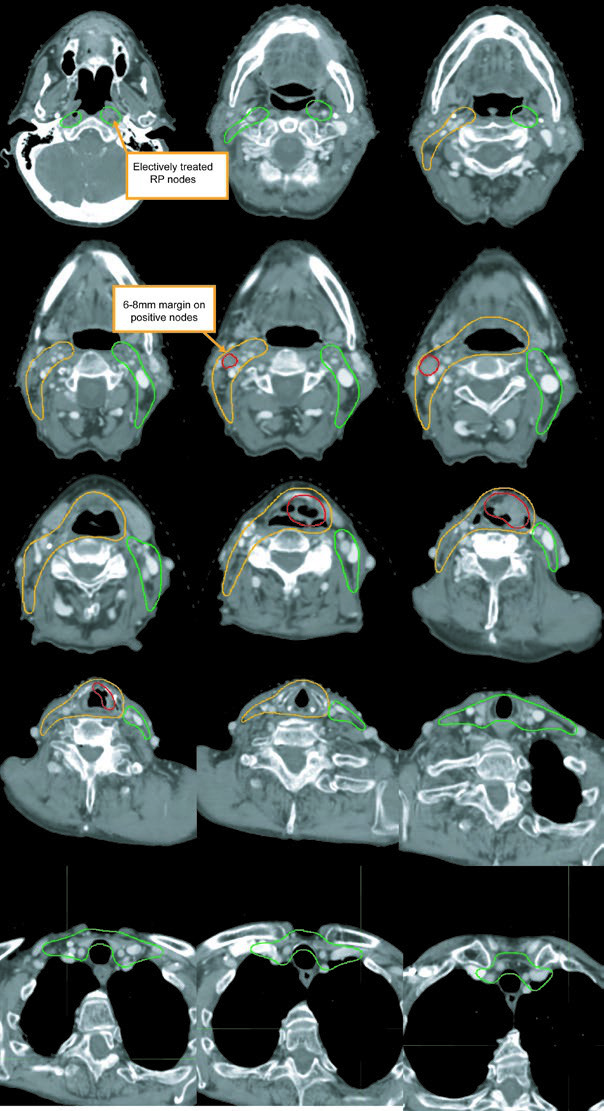

The GTV should be built from laryngoscopy, CT, MRI, and PET together. Positive neck nodes include those with central necrosis, extracapsular extension, or short-axis diameter greater than 1 cm. Borderline nodes with FDG avidity should be treated as involved disease. Small bean-shaped nodes with a fatty hilum are more likely benign, but enlarged retropharyngeal nodes should be considered positive even when they are small because that pattern is unusual enough to matter.

Advanced-stage disease: ≥T3 or node-positive

Once disease is T3 or higher, or the neck is involved, both necks belong in the plan. The preferred approach in the chapter is a sequential cone down: an initial 30-fraction plan delivers 54 Gy to low-risk subclinical disease and 60 Gy to high-risk subclinical disease, followed by 10 Gy in 5 more fractions to gross disease for a total of 70 Gy in 35 fractions. A single dose-painted IMRT plan is also acceptable, delivering 70 Gy, 63 Gy, and 54 Gy simultaneously over 35 days.

The subclinical primary CTV should cover the whole larynx from the bottom of the thyroid notch to the first tracheal ring, or farther inferiorly when needed. The subclinical nodal CTV should include at least levels II-IV and, in many cases, level VI. In the elective node-negative neck, the superior extent of level II stops where the posterior belly of the digastric crosses the internal jugular vein, corresponding to the caudal edge of the lateral process of C1. In the node-positive neck, level II should extend to the skull base and include the ipsilateral retrostyloid nodes.

| CTV 54-60a | Should encompass the entire GTV. Includes the entire larynx, from the bottom of the hyoid or the top of the thyroid notch to the bottom of the cricoid cartilage, with further inferior extension when needed. High-risk nodal regions include levels II-IV and the retrostyloid space on the involved node-positive neck. In the node-positive neck, level II should be treated to the base of skull. Level VI should be included if there is subglottic extension or a trach. |

| CTV 54b | Levels II-IV of the uninvolved neck. In the node-negative neck, the superior border of level II stops where the posterior belly of the digastric crosses the internal jugular vein, or at the caudal edge of the lateral process of C1. Levels IB and V are not included unless there is gross disease at those levels. Retropharyngeal nodes may be covered at physician discretion on the side of bulky adenopathy because of retrograde flow. Level VII coverage is recommended for subglottic extension or hypopharyngeal involvement. |

Levels IB and V are not elective by default and are only included when gross disease is present there. Retropharyngeal nodes may be covered on the side of bulky adenopathy at physician discretion. Level VII is recommended for subglottic extension or hypopharyngeal involvement. That is one of the most useful parts of the chapter because it turns abstract spread patterns into concrete cranial and caudal borders.